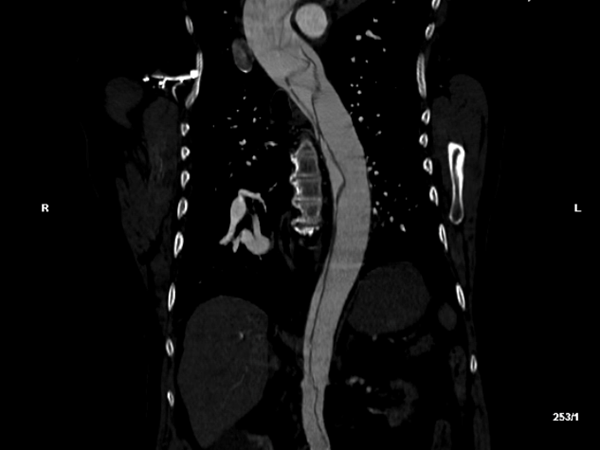

Based on these exam findings, an emergent CTA of the aorta was obtained, and demonstrated an extensive type A dissection involving the aortic valves, all 3 arch vessels, the right coronary artery, and the right common iliac artery with loss of signal at the right external and femoral arteries. The celiac, inferior mesenteric, and left renal arteries were all supplied by false lumens.

Figure 1: Transverse (left) and sagittal (right) sections of the patient’s initial computed tomography radiographic study, demonstrating a complex aortic dissection flap extending from the aortic valve through the iliac bifurcation.